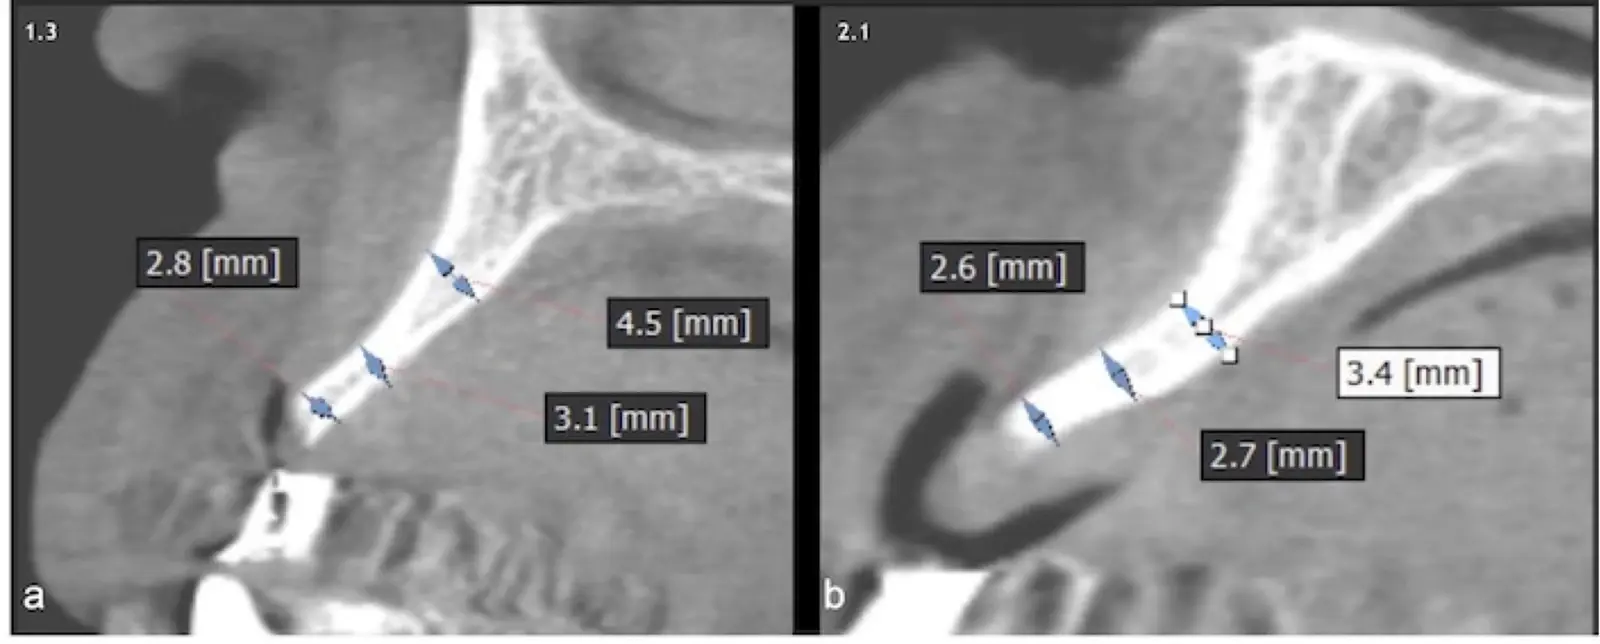

En las imágenes superiores se aprecia una reconstrucción de reborde con injertos en bloque previo a la planificación de implantes; en las imágenes inferiores, se observa la deficiencia vertical del reborde óseo y el tratamiento realizado con el piezoeléctrico.

Figura 34. Vista frontal donde se observa deficiencia vertical del reborde óseo a nivel de las piezas 2.1, 2.2.

Figura 36. Defecto óseo y severa reabsorción ósea horizontal: vista clínica (a) y corte tomográfico (b).